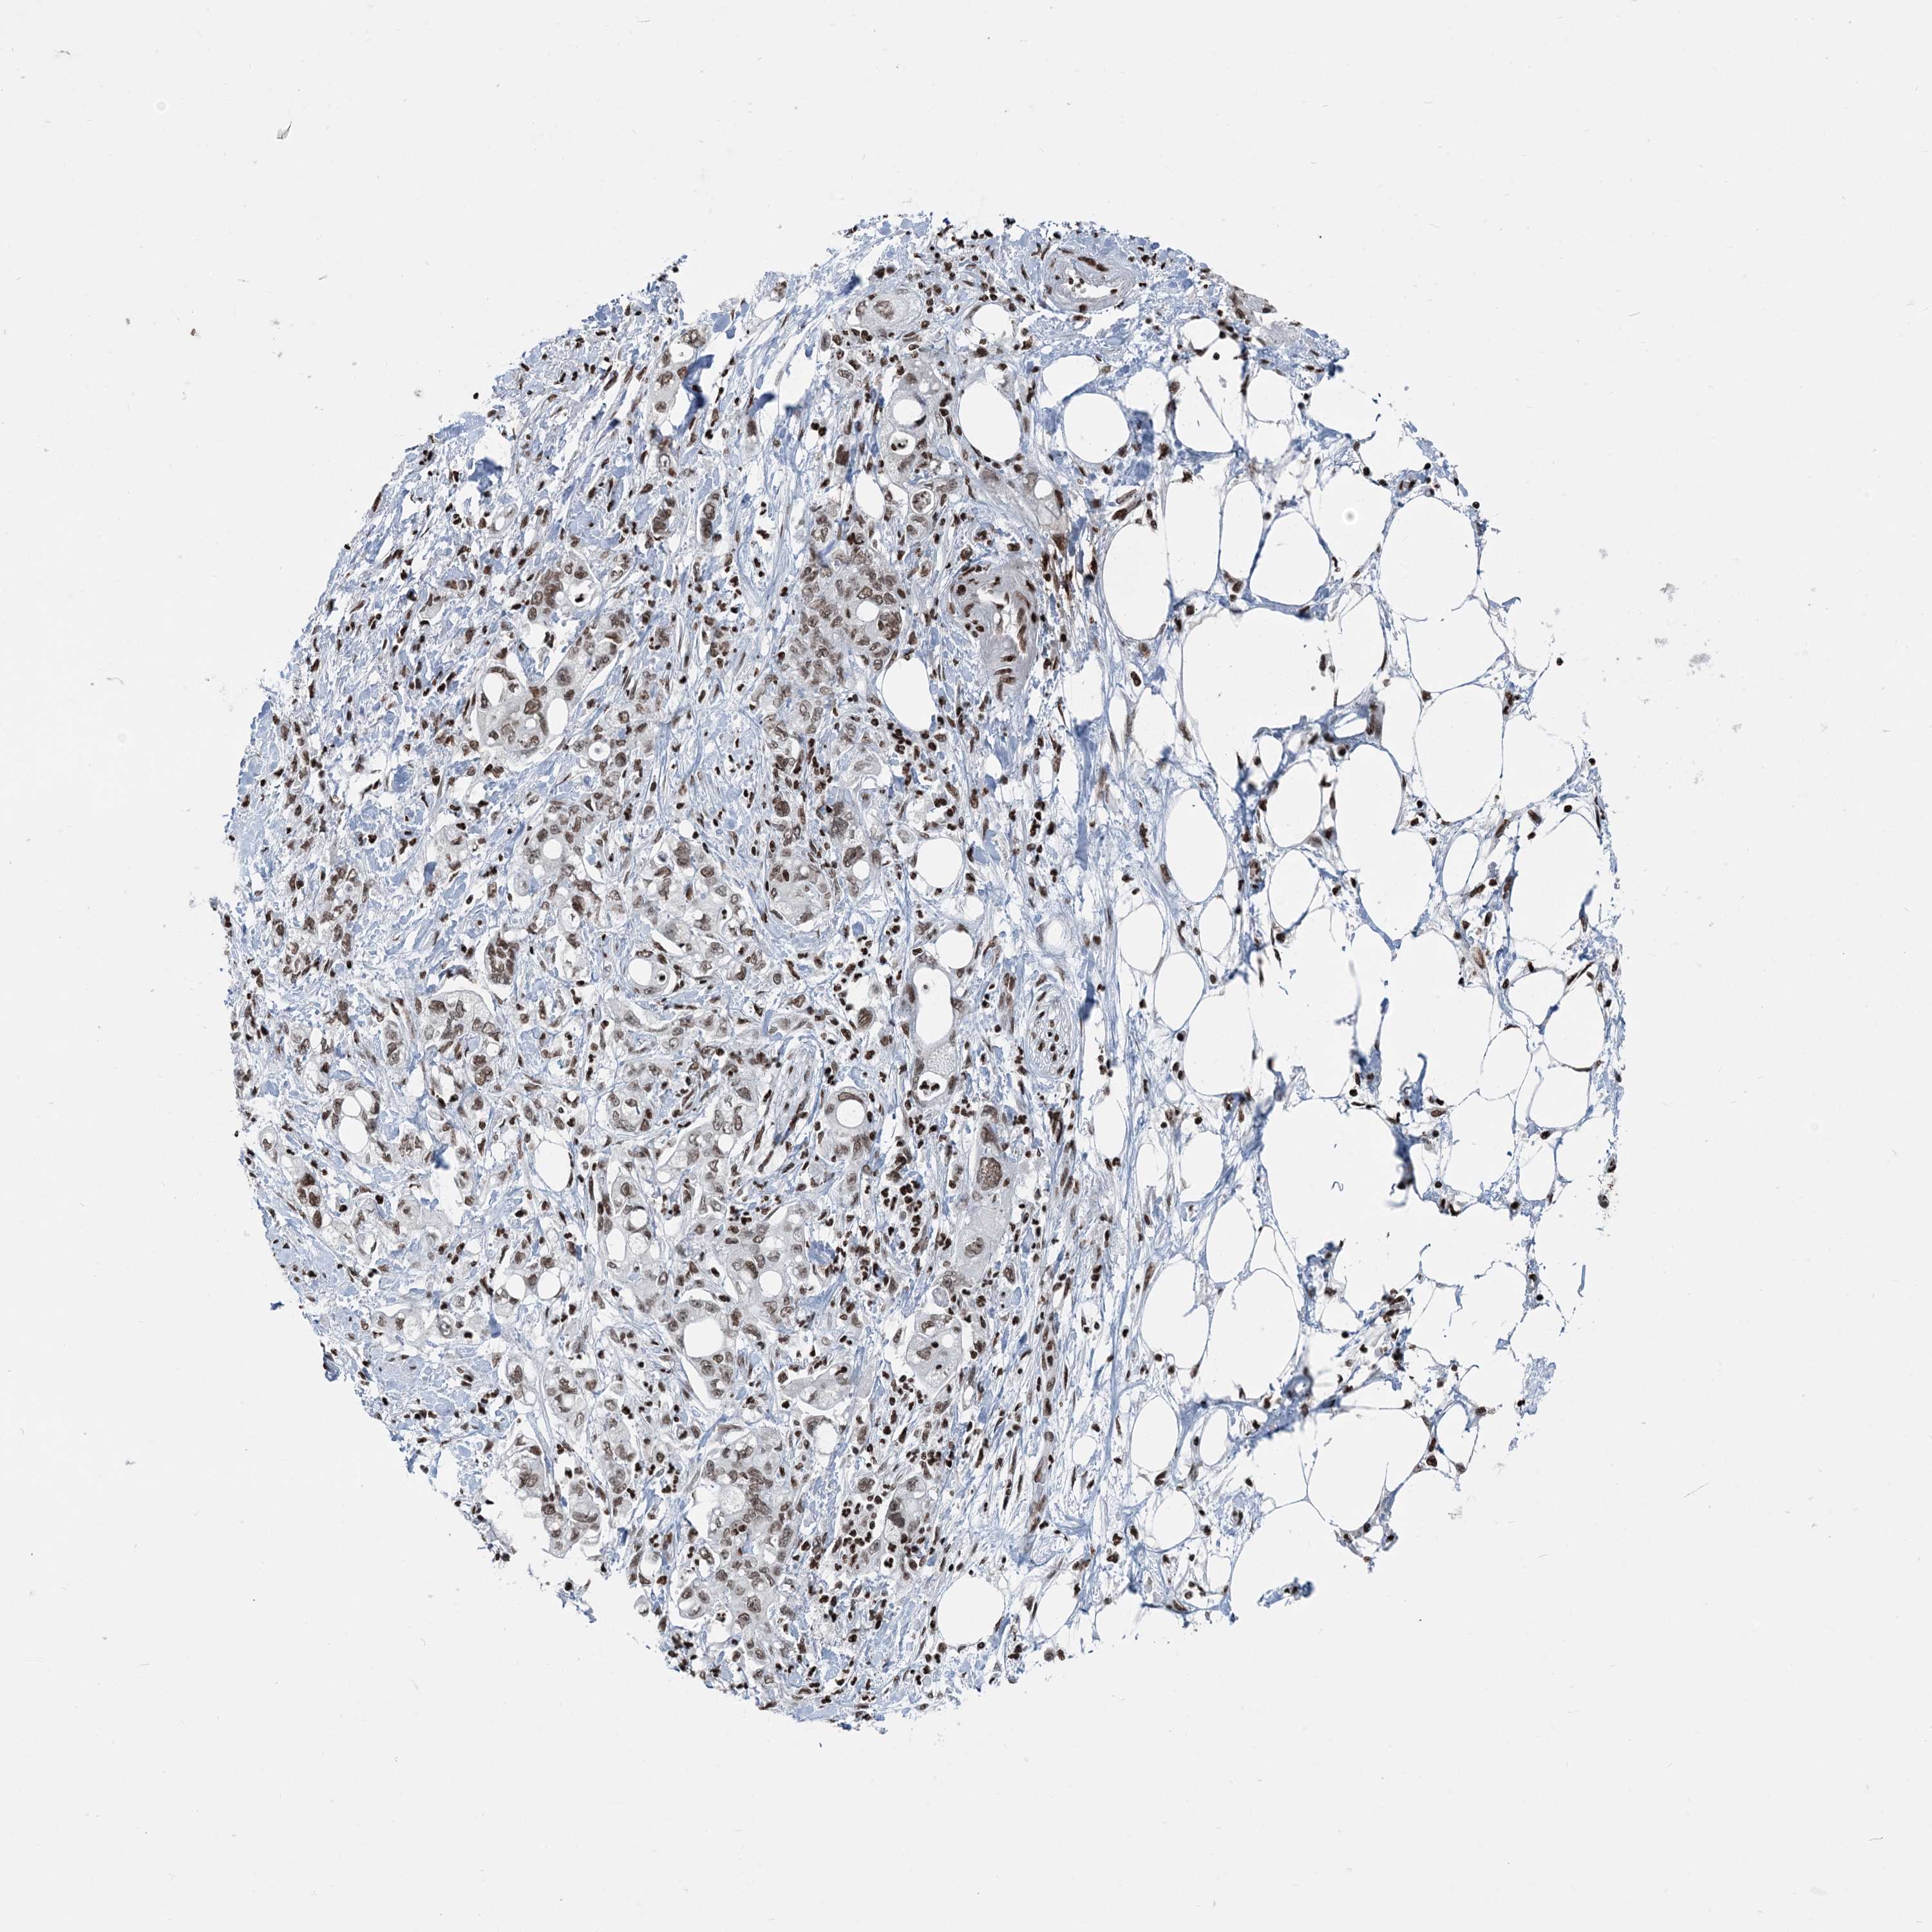

PANCREATIC CANCER - Protein expressioni

A mouse-over function shows sample information and annotation data. Click on an image to view it in a full screen mode. Samples can be filtered based on level of antibody staining by selecting one or several of the following categories: high, medium, low and not detected. The assay and annotation is described here.

Note that samples used for immunohistochemistry by the Human Protein Atlas do not correspond to samples in the TCGA dataset.

Antibody stainingi

Antibody staining in the annotated cell types in the current human tissue is reported as not detected, low, medium, or high, based on conventional immunohistochemistry profiling in selected tissues. This score is based on the combination of the staining intensity and fraction of stained cells.

Each image is clickable and will lead to virtual microscopy that enables deeper exploration of all samples and also displays staining intensity scores, fraction scores and subcellular localization as well as patient and tissue information for each sample.

Antibody HPA042570

Antibody CAB037166

Antibody CAB037187

Antibody CAB037221

Staining

High

Medium

Low

Not detected

Intensity

Strong

Moderate

Weak

Negative

Quantity

>75%

75%-25%

<25%

None

Location

Nuclear

Cytoplasmic/membranous

Cytoplasmic/membranous,nuclear

Adenocarcinoma, NOS